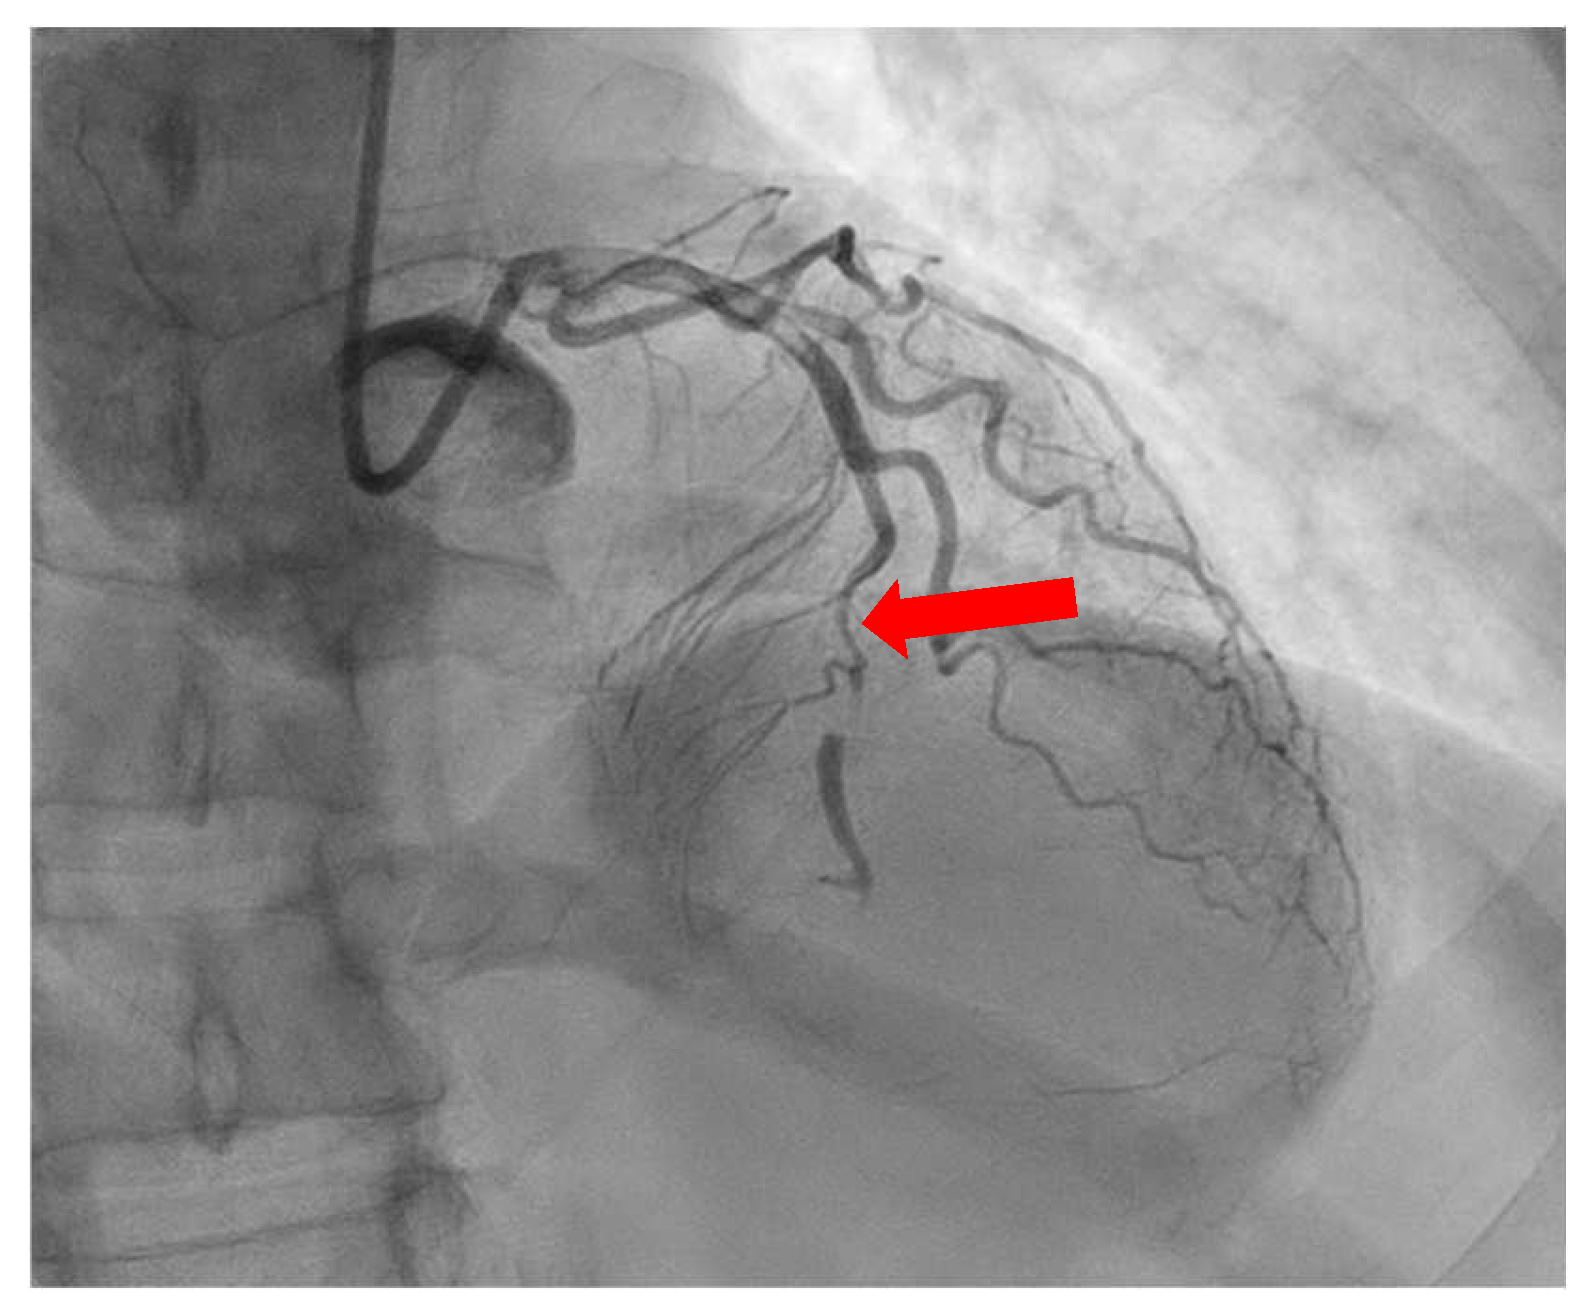

- Gupta, S.; Meyersohn, N.M.; Wood, M.J.; Steigner, M.L.; Blankstein, R.; Ghoshhajra, B.B.; Hedgire, S.S. Role of Coronary CT Angiography in Spontaneous Coronary Artery Dissection. Radiol. Cardiothorac. Imaging 2020, 2, e200364. [Google Scholar] [CrossRef]

- Aslam, A.; Stojanovska, J.; Khokhar, U.S.; Weinberg, R.L.; Ganesh, S.K.; Labounty, T.; Sutton, N.R.; Patel, S. Spontaneous Coronary Artery Dissection: An Underdiagnosed Clinical Entity-A Primer for Cardiac Imagers. RadioGraphics 2021, 41, 1897–1915. [Google Scholar] [CrossRef]

- Marrazzo, G.; Palermi, S.; Pastore, F.; Ragni, M.; De Luca, M.; Gambardella, M.; Quaranta, G.; Messalli, G.; Riegler, L.; Pergola, V.; et al. Multimodality Imaging Approach to Spontaneous Coronary Artery Dissection. J. Clin. Med. 2022, 12, 154. [Google Scholar] [CrossRef]

- Sun, Y.; Mao, D.; Lu, F.; Chen, Y.; Shi, K.; Qi, L.; Guo, X.; Hua, Y. Diagnosis of Dissection of the Coronary Artery Dissection by Multidetector Computed Tomography: A Comparative Study with Coronary Angiology. J. Comput. Assist. Tomogr. 2015, 39, 572–577. [Google Scholar] [CrossRef]

- Roura, G.; Ariza-Solé, A.; Rodriguez-Caballero, I.F.; Gomez-Lara, J.; Ferreiro, J.L.; Romaguera, R.; Teruel, L.; de Albert, M.; Gomez-Hospital, J.A.; Cequier, A. Noninvasive Follow-Up of Patients with Spontaneous Coronary Artery Dissection with CT Angiography. JACC Cardiovasc. Imaging 2016, 9, 896–897. [Google Scholar] [CrossRef]

- Tweet, M.S.; Akhtar, N.J.; Hayes, S.N.; Best, P.J.; Gulati, R.; Araoz, P.A. Spontaneous Coronary Artery Dissection: Acute Findings on Coronary Computed Tomography Angiography. Eur. Heart J. Acute Cardiovasc. Care 2019, 8, 467–475. [Google Scholar] [CrossRef]

- Bin Saeedan, M.; Ramchand, J.; Bolen, M. Role of Computed Tomography Angiography in Setting of Spontaneous Coronary Artery Dissection. Curr. Probl. Diagn. Radiol. 2021, 50, 532–539. [Google Scholar] [CrossRef]